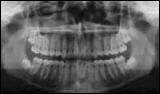

- Röntgenübersichtsaufnahme mit geringer Strahlendosis. Die Aufnahme liefert wertvolle Informationen über die Anzahl der Zähne, deren Lage und eventuelle anatomische Besonderheiten.

Röntgen-Übersichtsaufnahme